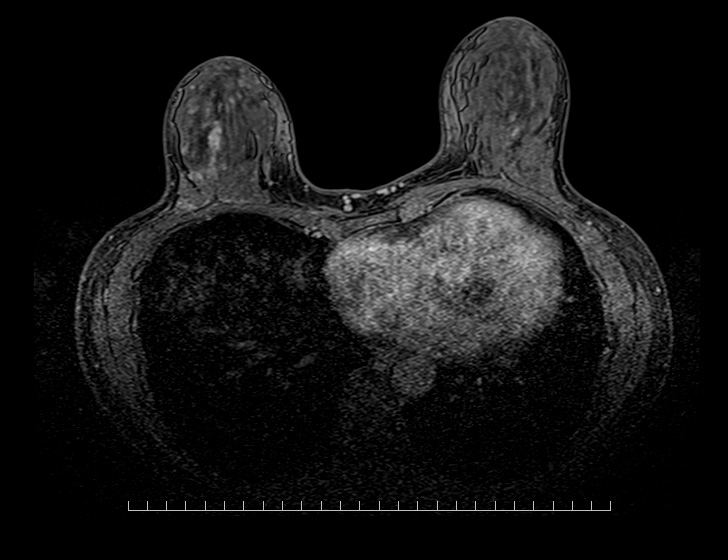

MRIとは、(MRI=MagneticResonanceImaging:磁気共鳴画像診断装置)の略です。MRIは、強力な磁石でできた筒の中に入り、強い磁石とラジオに使われているような電波を用いて体内の状態を画像にする検査です。特に脳や脊椎、四肢、子宮、卵巣、前立腺といった骨盤内の病変に関して優れた検出能力を持っています。

| 撮影可能な部位 | 頭部、脊椎、乳腺、腹部、骨盤部、関節など 全身領域 |

MRI検査依頼書(PDF)当院で撮影したMRI画像